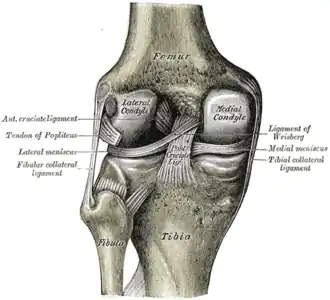

Pathophysiology

The knee joint is formed by three bones: the femur (thighbone), the tibia (shinbone), and the patella (kneecap). These bones are held together by ligaments, which are strong bands of tissue that keep the joint stable while an individual is walking, running, jumping, etc. There are two types of ligaments in the knee: the collateral ligaments and the cruciate ligaments.

The collateral ligaments include the medial collateral ligament (along the inside of the knee) and the lateral or fibular collateral ligament (along the outside of the knee). These two ligaments function to limit sideways movement of the knee.[6]

The cruciate ligaments form an “X” inside the knee joint with the anterior cruciate ligament running from the front of the tibia to the back of the femur, and the posterior cruciate ligament running from the back of the tibia to the front of the femur. The anterior cruciate ligament prevents the tibia from sliding out in front of the femur and provides rotational stability.[6]

There are also two C-shaped structures made of cartilage called the medial meniscus and lateral meniscus that sit on top of the tibia in the knee joint and serve as cushion for the bones.[1]

|

| Right knee, front, showing interior ligaments | Left knee, behind, showing interior ligaments |